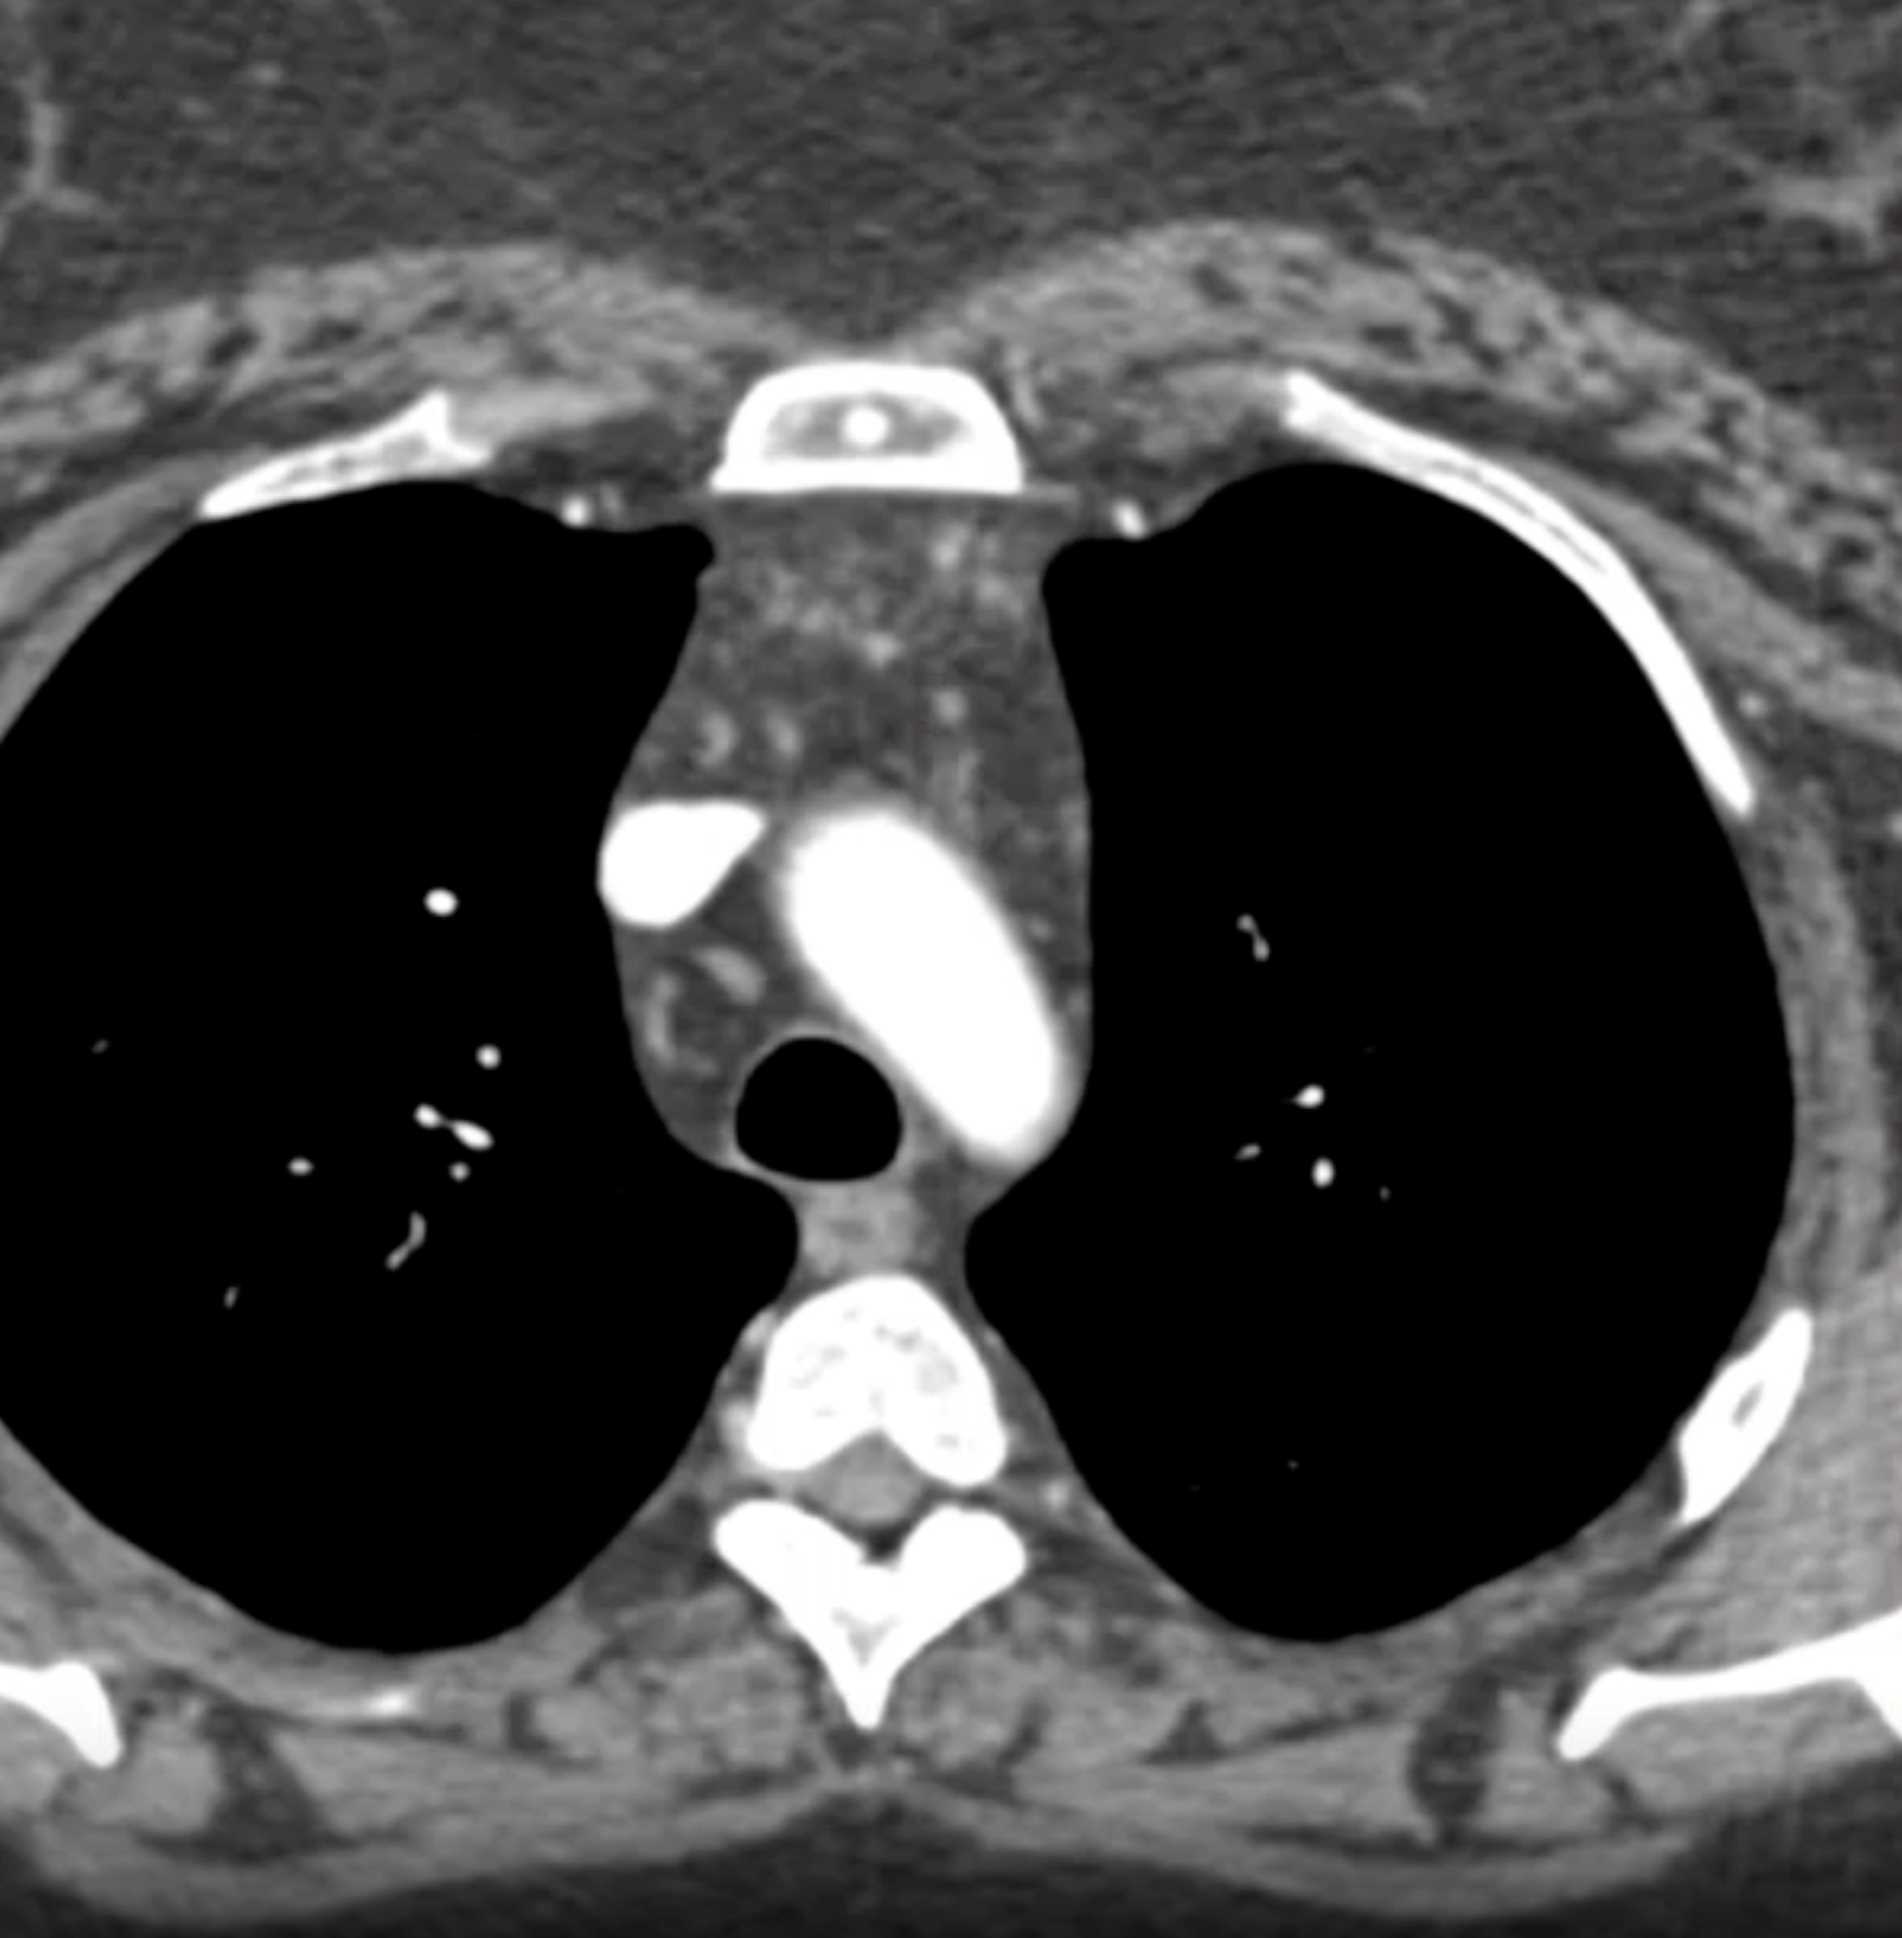

Thymolipoma